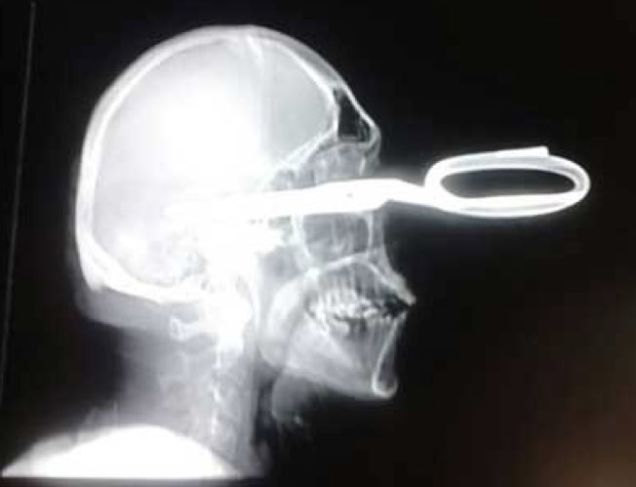

The attacker ran off while Acevedo Monroy's buddy drove him to a local hospital, where the above X-ray was produced.

"At first we thought it was some sort of joke, but then he fainted and we rushed him into emergency," a hospital official told CEN, "He had been stabbed in the upper-left side of his skull and the scissors had penetrated his parietal brain lobe. He is lucky to be alive."